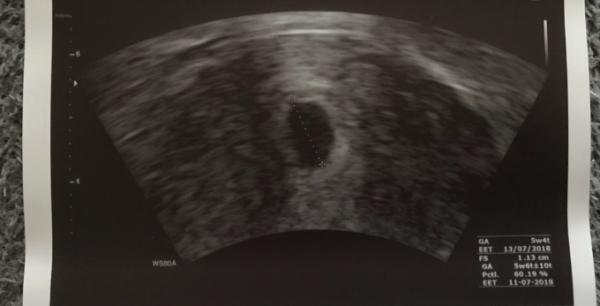

Die vielen , vielen Dank , fĂŒr Eure lieben , aufbauenden Worte . War heute wieder zur Kontrolle und man hat endlich , eine 1,13 cm große FruchthĂŒlle , in der GebĂ€rmutter,gesehen Laut meiner letzten Periode bin ich 5W4T laut Ultraschall 5W6T, also zeitgerecht . Ich hab ganz dolle geweint vor Freude , die ganze Anspannung ist von mir abgefallen . Erstmal also Entwarnung . Nun muss ich in einer Woche wieder hin und hoffe dann Dottersack und WĂŒrmchen zu sehen. Vielleicht wird ja doch alles gut Das einzige was mir im Moment noch etwas Sorgen und auch leichte Schmerzen bereitet ist die Gelbkörperzyste, die auf 5,5 cm gewachsen ist . Ich soll mich körperlich schonen , damit sie nicht platzt .

Bild zu